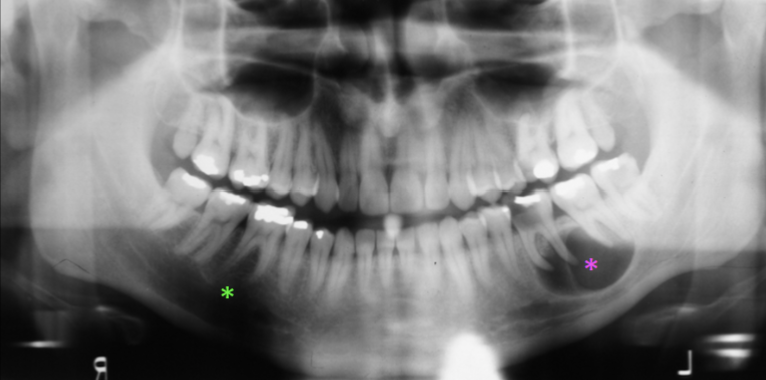

What is the Green Dot?

Submandibular Fossa

What is the Purple Dot?

Radicular Cyst